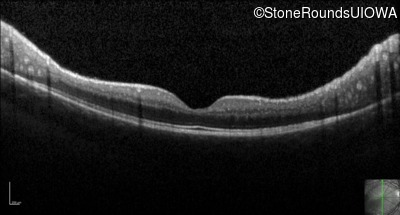

Optical Coherence Tomography - Left - 20/32

Exemplar / OCT Stack